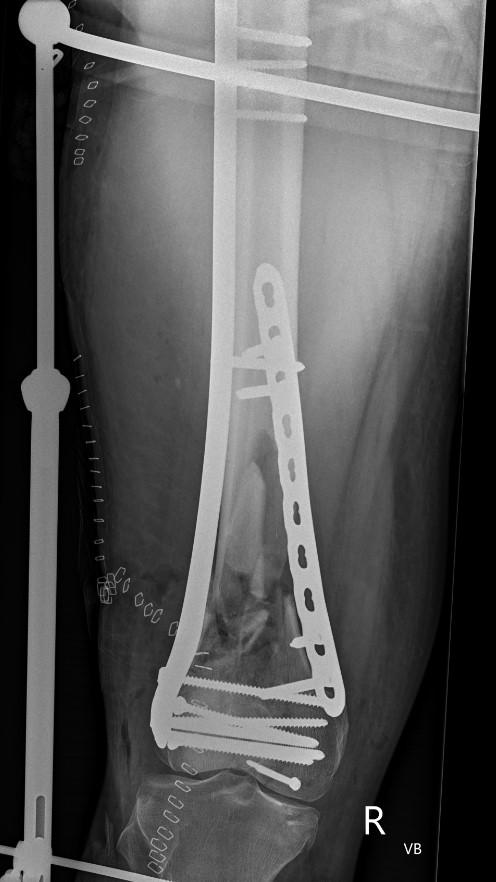

Type C: Complete articular

Xray / CT

Options

Dual Plate

Plate + Retrograde nail

Indications

Significant comminution

Loss of medial cortical buttress